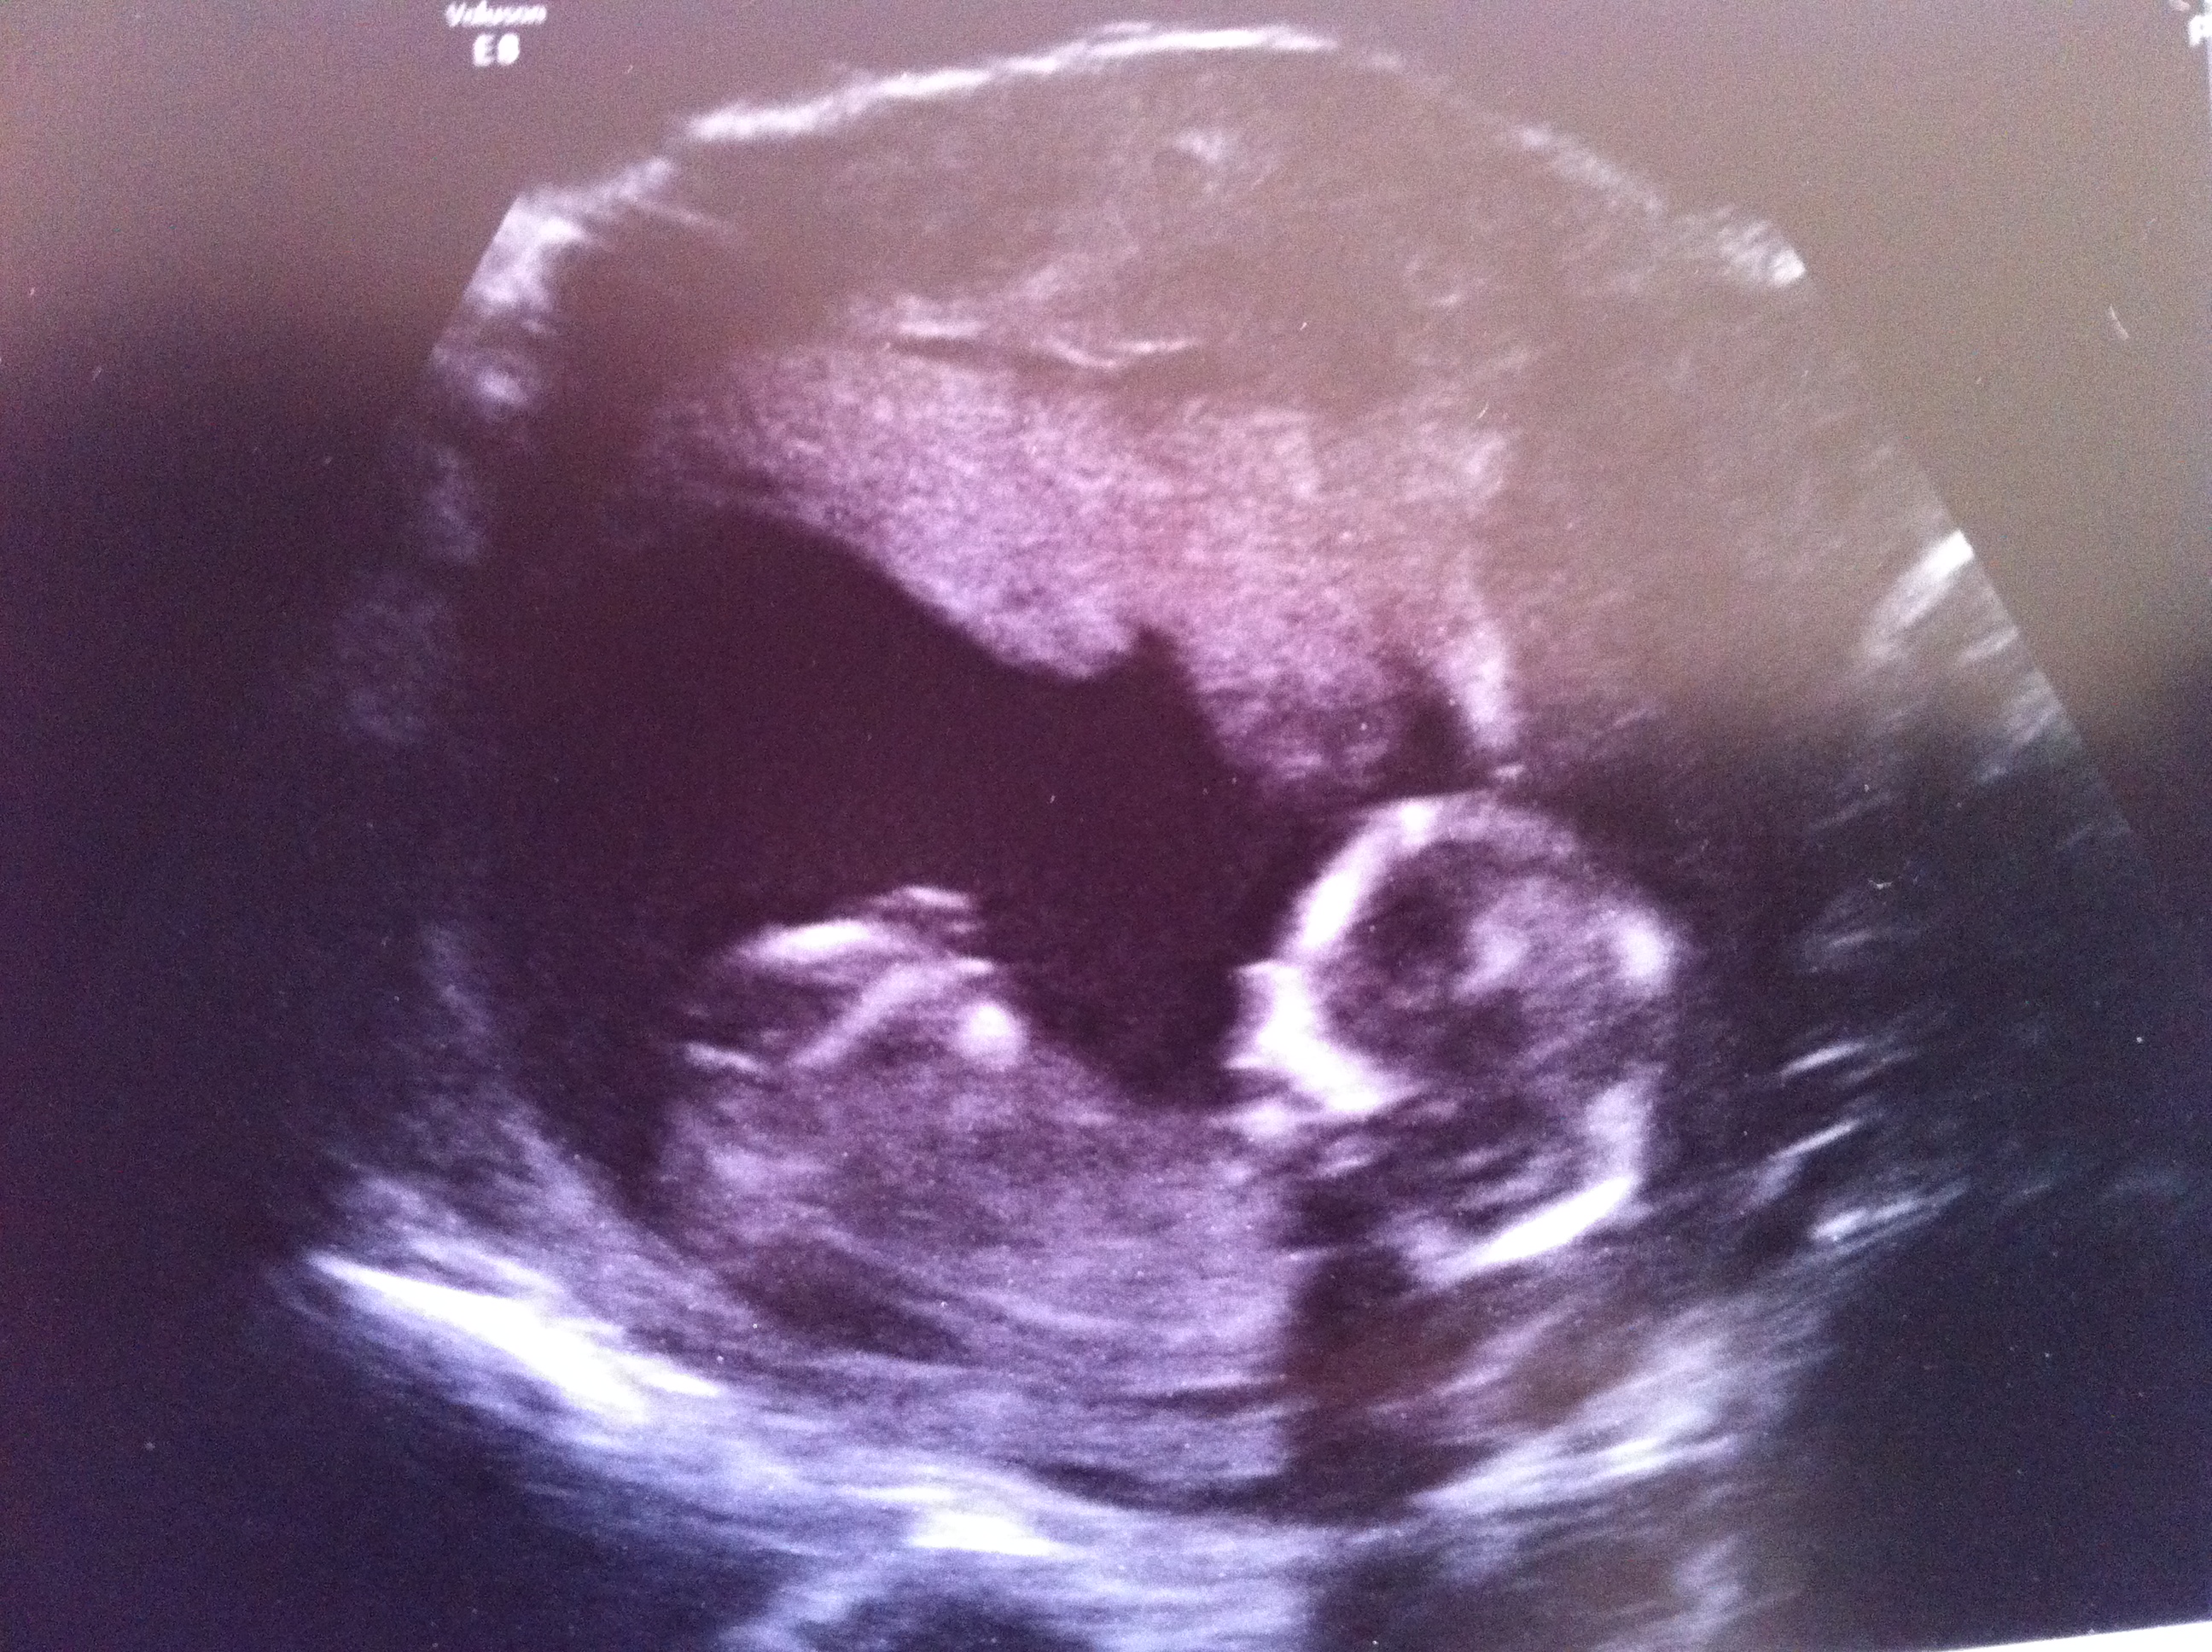

Girl

Very flat girly nub there!

Thankyou ladies for having a look. Your opinions are very much appreciated. Can't believe I was lucky enough to be given pictures which included the nub. It was very obvious during the scanning that the nub was long and flat. When I saw the potty shot there was definitely nothing between the legs. All I saw was a flat horizontal bright White line? I was to afraid to ask for a gender guess and won't be finding out at the next scan either. X